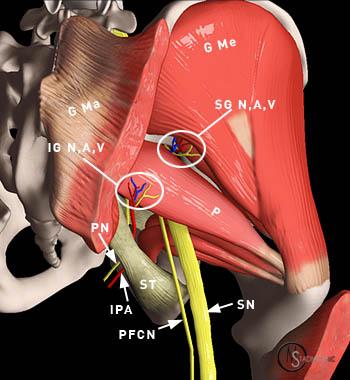

radiculpathy

ممكن يبقى هو المسبب

أمر اخير وهو radiculpathy and trigger points

انا نزلت ابحاث عنه قبل كده واتكلمنا فيه

وده مش معناه أن مجرد ما اشتغل ع radiculpathy أنه يبقى centralized والمشاكل دى تتظبط

يبقى معناه أن TP اتحلت

لا دى هتاخد نصيب من شغل therapeutic ex and myorelaese and ichemic press

و MeT ع العضلة ككل وع TP

فاحنا مش بنشتغل ف اتجاه واحد فقط ولا نمسك الموضوع من أطرافه وخلاص كده